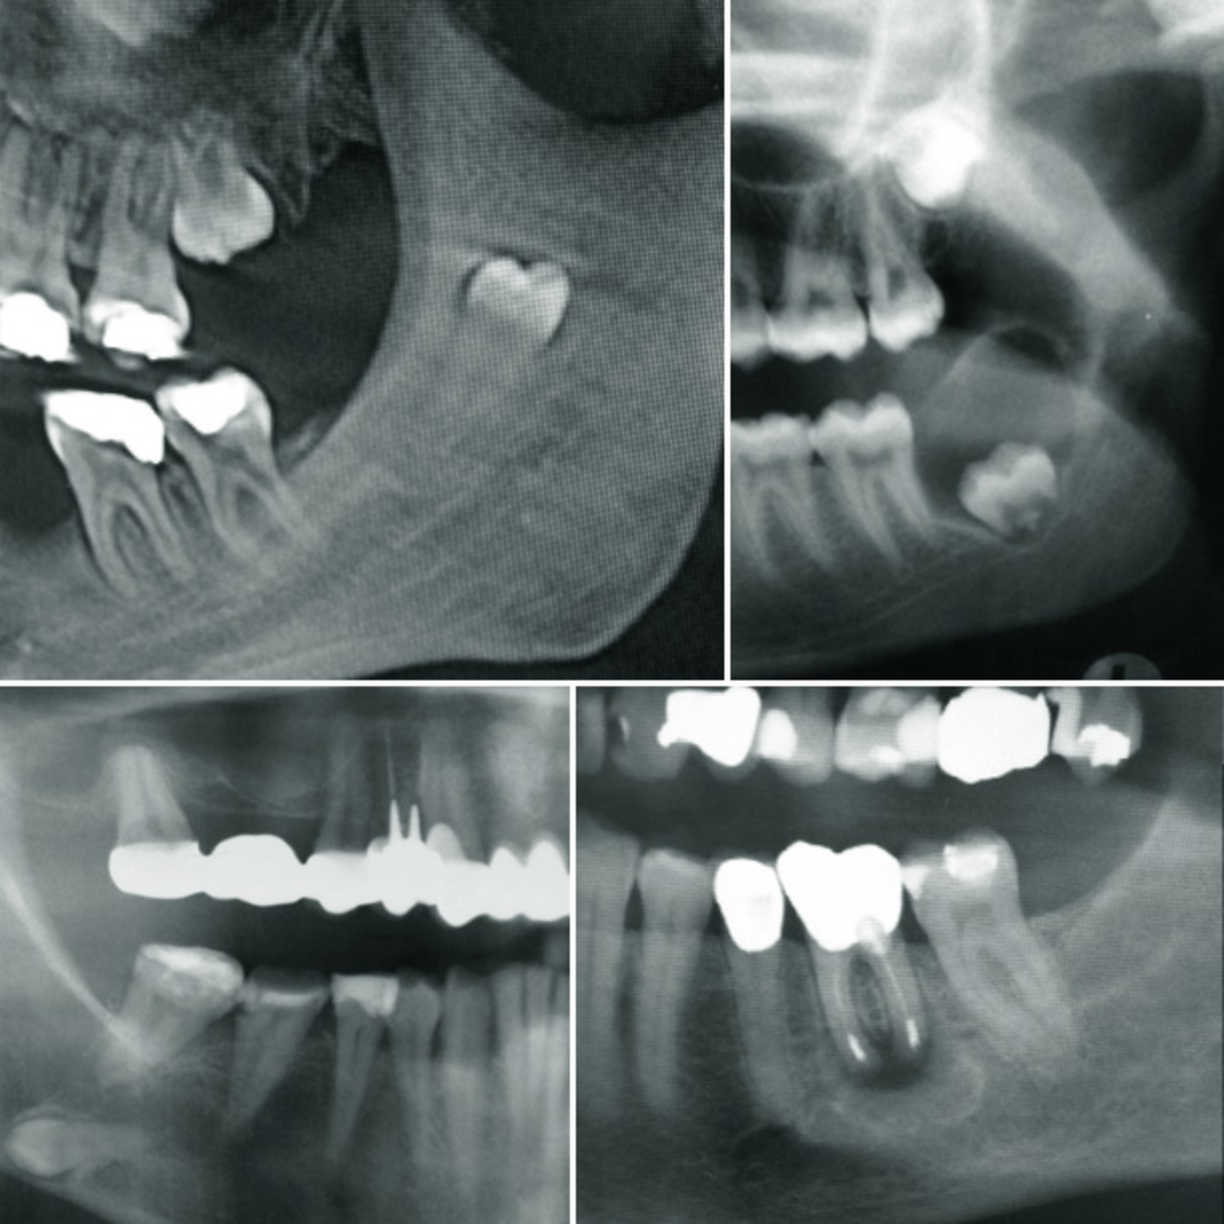

Manchmal kann es notwendig sein, dass für eine komfortable und schmerzfreie Kaufunktion des Kiefers ein Zahn nur durch eine chirurgische Maßnahme erhalten werden kann, bzw. entfernt werden muss. Die Vorstellung, dass eine solche Maßnahme bevorsteht, führt bei vielen Patienten zu einem schlechten Gefühl. Wir in der Praxis Dres. Petersen möchten dieses Erlebnis für Sie so schonend und atraumatisch wie möglich gestalten. Dazu nutzen wir individuell auf den Patienten zugeschnittene Anästhesie- und Behandlungsmethoden. Unter besonderen Umständen kann eine solche Methode auch in Kooperation mit der Tagesklinik am Meer in Bremerhaven in Vollnarkose durchgeführt werden. Unser Behandlungsspektrum umfasst hier die gesamte Oralchirurgie: knochenschonende Zahn- und Weisheitszahnentfernungen, Wurzelspitzenresektionen, Zystenentfernungen, Implantationen mit und ohne Knochenaufbauten, Wiederherstellung der Kaufunktion, Explantationen, chirurgische Behandlungen zur langfristigen Erhaltung des Zahnfleischs und der Zähne, Diagnostik und Erkennung von gut- und bösartigen Erkrankungen der Mundschleimhäute und des Knochens, Behandlung von Knirschern, etc.